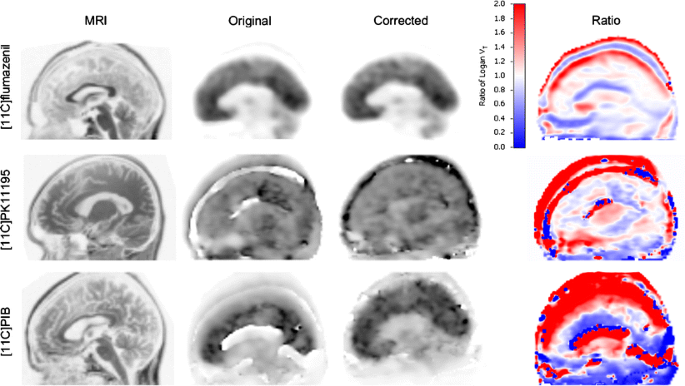

Fig. 8

figure 8

Differences in VT images generated from clinical PET scans with large movements before and after motion correction. From left to right: MRI, parametric VT images before (original) and after motion correction and ratio image (corrected divided by original) for [11C]flumazenil (top row), (R)-[11C]PK11195 (middle row) and [11C]PIB (bottom row)

For both (R)-[11C]PK11195 (Fig. 8, middle row) and [11C]PIB (Fig. 8, bottom row), major differences were seen between VT images before and after motion correction with large artefacts in the uncorrected VT image. The large difference between original and corrected images is also clearly visible in the ratio image of both VT images (Fig. 8, middle row, last column). For [11C]PIB, differences were even more pronounced (Fig. 8, bottom row). At a regional level quantitative differences were as high as 433% (right thalamus). Across all regions, the average difference was 85 ± 121%. Supplementary movie S2 shows the original [11C]PIB data set and the [11C]PIB data set after motion correction. Quantitative differences for (R)-[11C]PK11195 were smaller, with a maximum of 49% (parietal lobe) and an average (across all anatomical regions) of 14.9 ± 15.1%.

Minor movements

Parametric VT images before and after motion correction, together with corresponding MRI images, for data sets with no or minor movements are shown in Fig. 9. No visual differences between images before and after motion correction could be seen. However, for [11C]flumazenil (Fig. 9, top row), the ratio image suggests that there was some (small) motion present in the original data set. For [11C]flumazenil, the largest difference at regional level was found for right caudate (10.9%), but averaged over all regions differences were only 3.6 ± 3.8%. For both (R)-[11C]PK11195 (Fig. 9, middle row) and [11C]PIB (Fig. 9, bottom row), only small differences were found (max. 4.3%). On average, over all regions, differences between VT before and after motion correction were 0.4 ± 0.4% and 1.5 ± 1.3% for (R)-[11C]PK11195 and [11C]PIB, respectively.

Fig. 9

figure 9

Differences in VT images generated from clinical PET scans with no or minor movements before and after motion correction. From left to right: MRI, parametric VT images before (original) and after motion correction and ratio image (corrected divided by original) for [11C]flumazenil (top row), (R)-[11C]PK11195 (middle row) and [11C]PIB (bottom row)